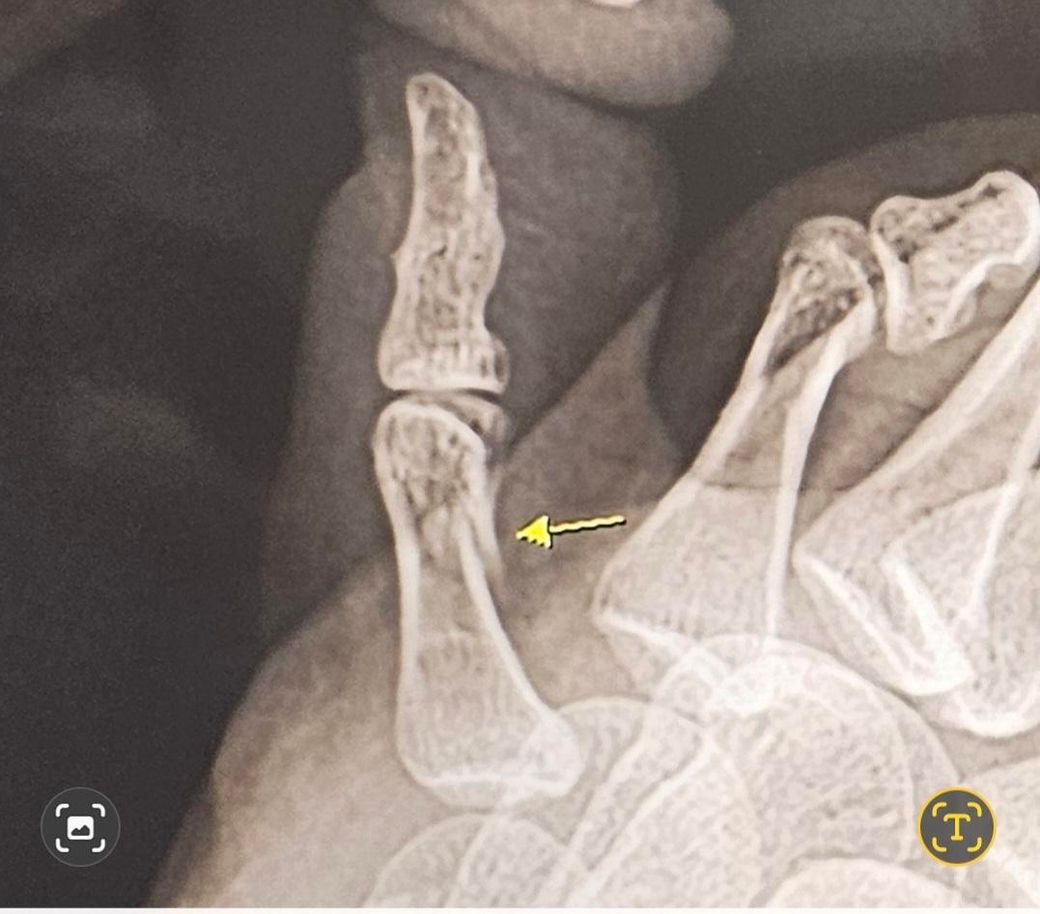

새끼발가락 골절 비수술 상태봐주셔요..

새끼발가락 골절되어 비수술 및 입원중이며, 반깁스 10일, 통깁스 1일차입니다. 통깁스 말고 발가락이랑 발등에 걸쳐서 하는 그물망깁스하고 일상생활해도될까요?.. 제 골절이 많이 심한편인지요.. 통깁스가 너무무거워서 바꾸고싶네요..ㅜ

현재 엑스레이 사진인지, 다쳤을때 사진인지 알아야 할 것 같은데 처음찍은 엑스레이 골절의 상태가 눈으로 보일 정도면 아직은 통기브스가 안전하긴 합니다. 다만 전문의 판단하에 그물 기브스도 가능 할 것 같은데.. 상의 해보시는게 가장 정확합니다.

• 안녕하세요. 김경태 정형외과 전문의입니다.

꽤 많이 깨져보입니다.

전위는 그리 심해보이진 않아서 보존적치료로 결과가 좋을것 같습니다.

불편하셔도 캐스트를 하는게 맞습니다.